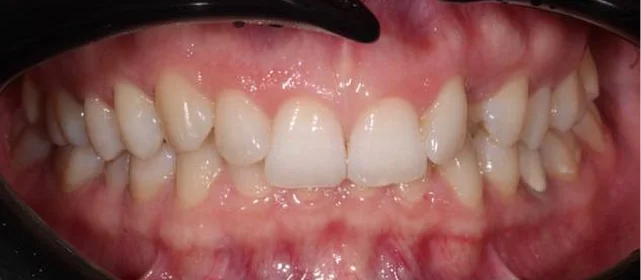

Обратилась с жалобой на скученность верхней и нижней челюсти средней степени тяжести — рецидив после подросткового лечения (ретейнер не носила).

КЛКТ, интраоральное сканирование, пародонтологическое обследование. Подвижности зубов нет, глубина зондирования — в пределах нормы.

Убыль кости — начальная, не превышает 1/4 длины корня.

рецессия десны в области нижних резцов, старые композитные пломбы на боковых зубах.